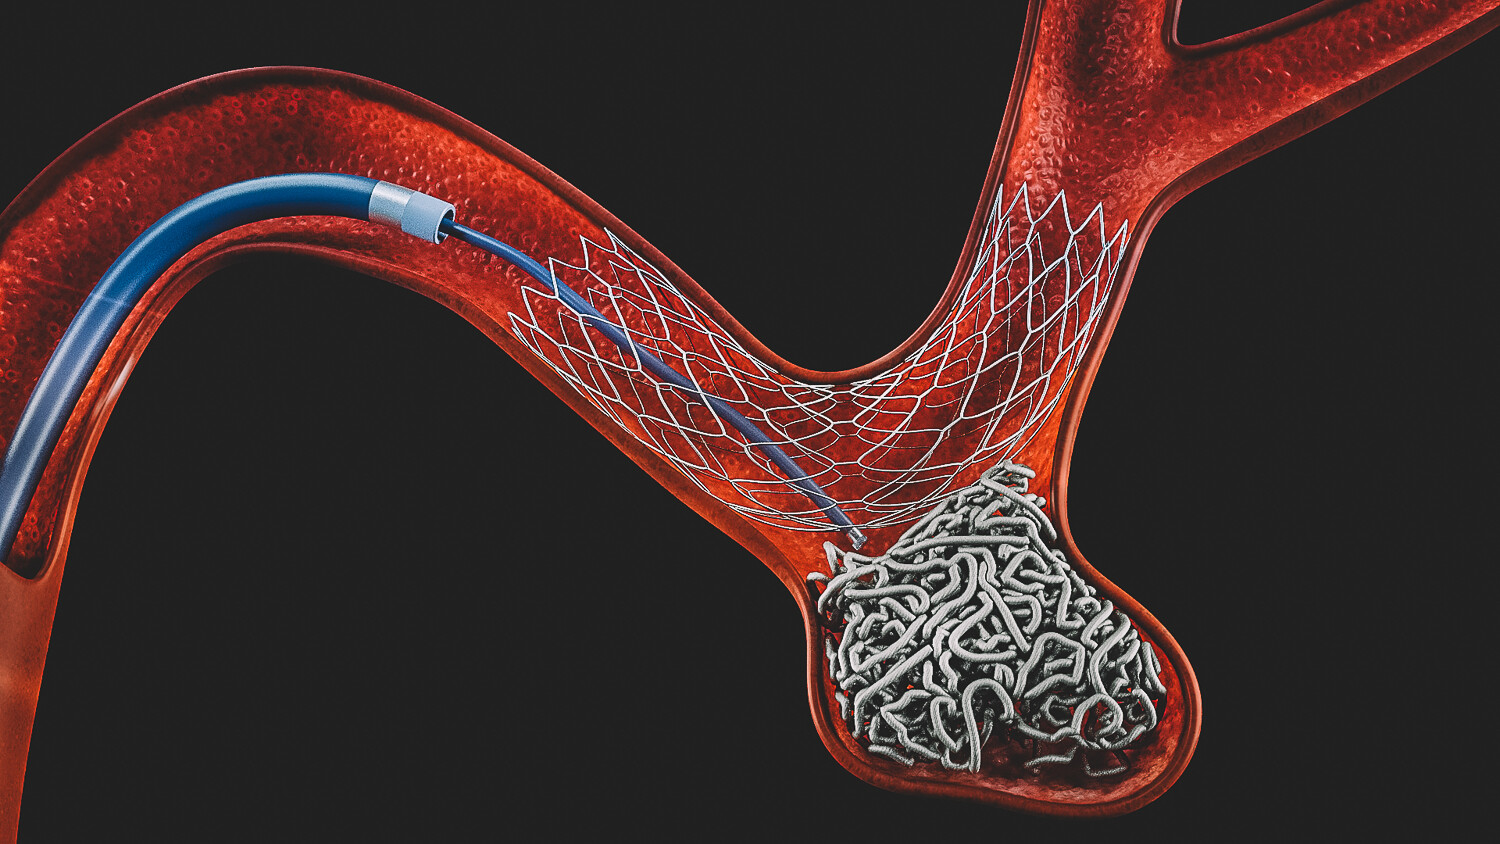

Tratamento endovascular

É um tipo de tratamento feito por dentro dos vasos, sem abrir a cabeça.

O médico acessa a artéria pela virilha ou pelo braço e chega até o aneurisma.

No local, são colocadas pequenas “molas” dentro do aneurisma.

O objetivo é fechar a “bolha / bexiga” por dentro, diminuindo o risco de rompimento.

É um método moderno, menos invasivo e, em muitos casos, com recuperação mais rápida.